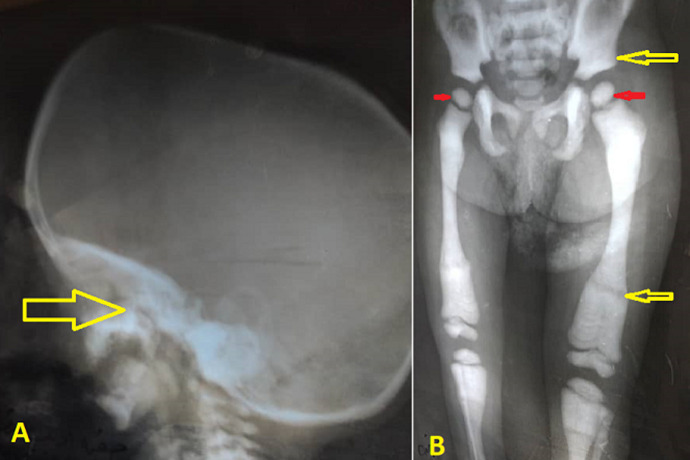

摘要婴儿恶性骨质疏松症是一种罕见的常染色体隐性遗传的骨吸收性疾病。它的特点是由于破骨细胞分化或功能失败导致骨密度增加。IMOP的临床表现从出生或婴儿期开始,根据骨质疏松的类型和程度有不同的环。我们提出了一个3岁的女性病人转介到我们由于慢性贫血六个月前。体格检查显示肝脾肿大,轴向张力低下,视力受损。血液检查显示全血细胞减少和低钙血症。影像学检查显示骨密度普遍增高,干骺端重塑异常,脑萎缩。骨髓穿刺(BMA)显示所有细胞系的干龙头和细胞增多。IMOP的诊断取决于临床、放射学和BMA结果。总之,IMOP是相对罕见的。准确的诊断应通过临床、BMA和放射学检查做出,特别是在资源有限的情况下,正如本病例所做的那样。

Infantile malignant osteopetrosis (IMOP) is a rare bone resorptive disorder with an autosomal recessive inheritance pattern. It is characterized by increased bone density due to osteoclastic failure in differentiation or function. The clinical manifestations of IMOP start at birth or infancy with varied rings according to the type and degree of osteopetrosis. We presented a 3-year-old female patient referred to us due to chronic anaemia six months ago. The physical examination revealed hepatosplenomegaly, axial hypotonia, and visual impairment. Blood investigation revealed pancytopenia and hypocalcemia. Radiologic studies revealed a generalized increase in bone density, abnormal metaphyseal remodelling, and rain atrophy. The bone marrow aspiration (BMA) shows dry tap and hypocellularity of all cell lines. IMOP was diagnosed depending on clinical, radiologic, and BMA results. In conclusion, IMOP is relatively uncommon. Accurate diagnosis should be made through clinical, BMA, and radiologic investigations, especially in a resource-limited setting, as performed in our case.